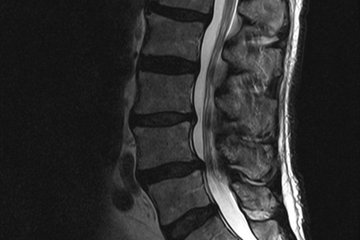

Wie bei allen Wirbelsäulenerkrankungen wird die Diagnose anhand einer Kernspintomographie (MRT) gestellt. Mit Hilfe der MRT kann Ort und Ausmaß der Verengung genau klassifiziert werden. Sollte diese Untersuchung bei bestimmten Patienten nicht möglich sein (z. B. Herzschrittmacherpatienten) kann auch eine CT Untersuchung Aufschluss geben.

Die im Fachjargon als „Spinalkanalstenose“ bezeichnete Verengung des Wirbelkanals, ist ein häufiges wirbelsäulenchirurgisches Krankheitsbild des älteren Patienten. Durch Vergrößerungen der Wirbelgelenke, der Bandstrukturen und Vorwölbungen der Bandscheibe kommt es zu einer Einklemmung der Spinalnerven bzw. des Rückenmarks. Eine Spinalkanalstenose ist normalerweise ein chronisch degenerativer Prozess, der im langfristigen Verlauf zunehmend ist und selten akut auftritt.

Bei Wirbelverengungen im Bereich der Lendenwirbelsäule kommt es typischerweise zu einer Reduktion der Gehstrecke (Claudicatio spinalis) die mit diffusen Schmerzen sowie einem Schwächegefühl der Beine einhergeht. In ausgeprägten Fällen kommt es auch zu „Ameisenlaufen“ bis hin zu echten Taubheitsgefühlen und Kraftdefiziten.